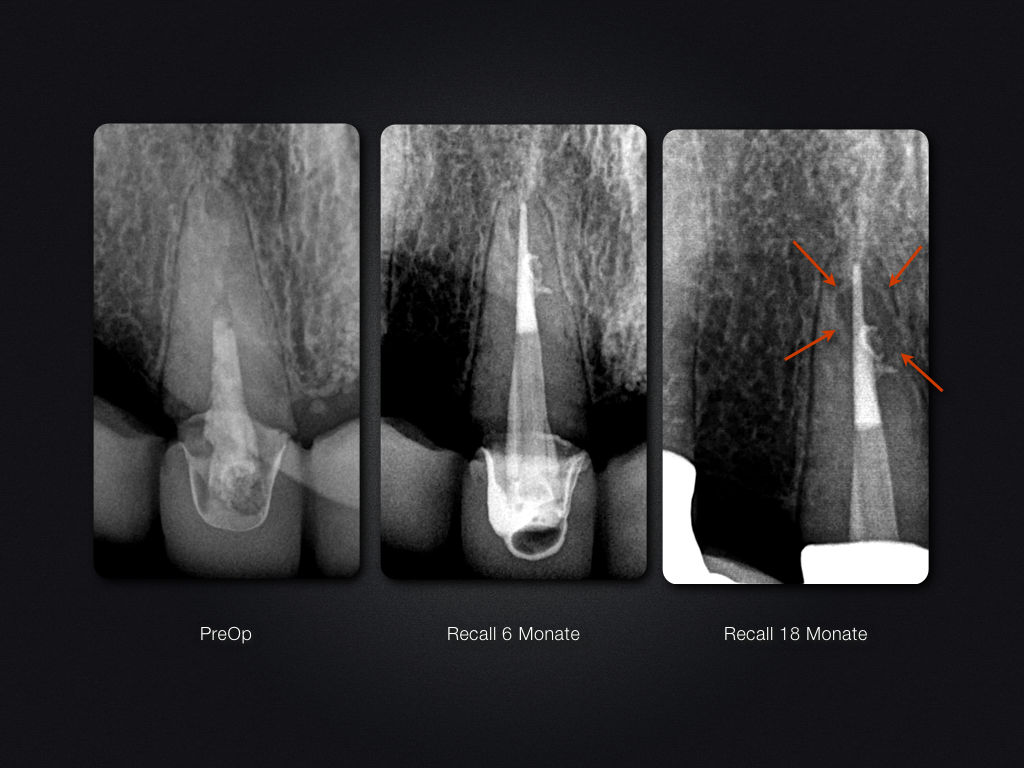

11D.006

Entwarnung